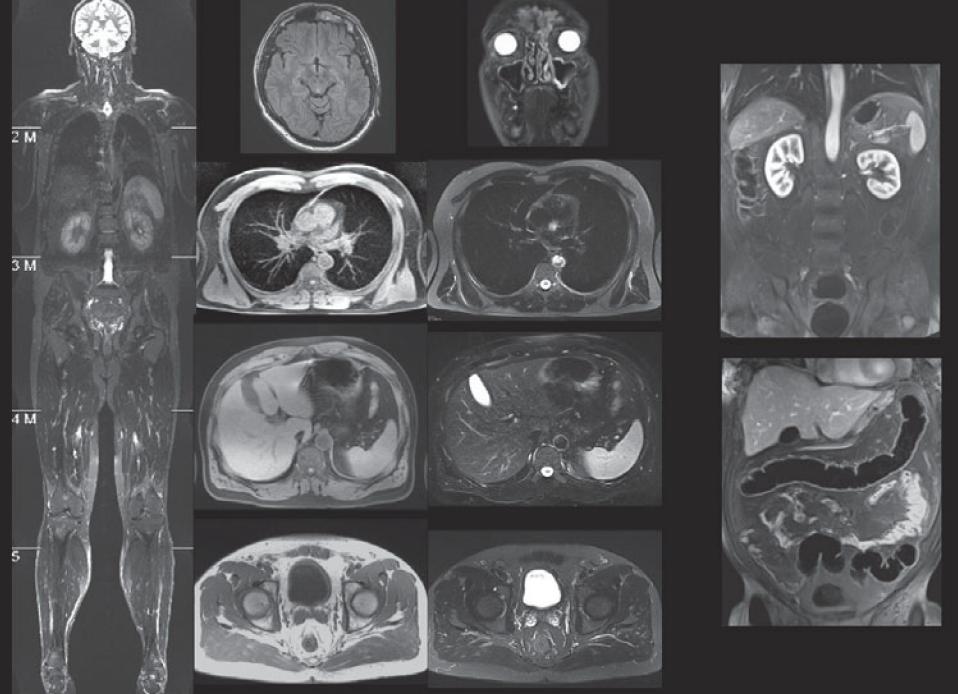

С помощью магнитно-ядерного резонанса можно осуществить диагностику любого сегмента человеческого тела, будь это коленный сустав, органы малого таза или поражённое болезнью лёгкое.

Метод при этом остаётся абсолютно безопасным для человека. Меняется только локализация сканирования, режимы его проведения, проекции и ракурсы, количество необходимых срезов.